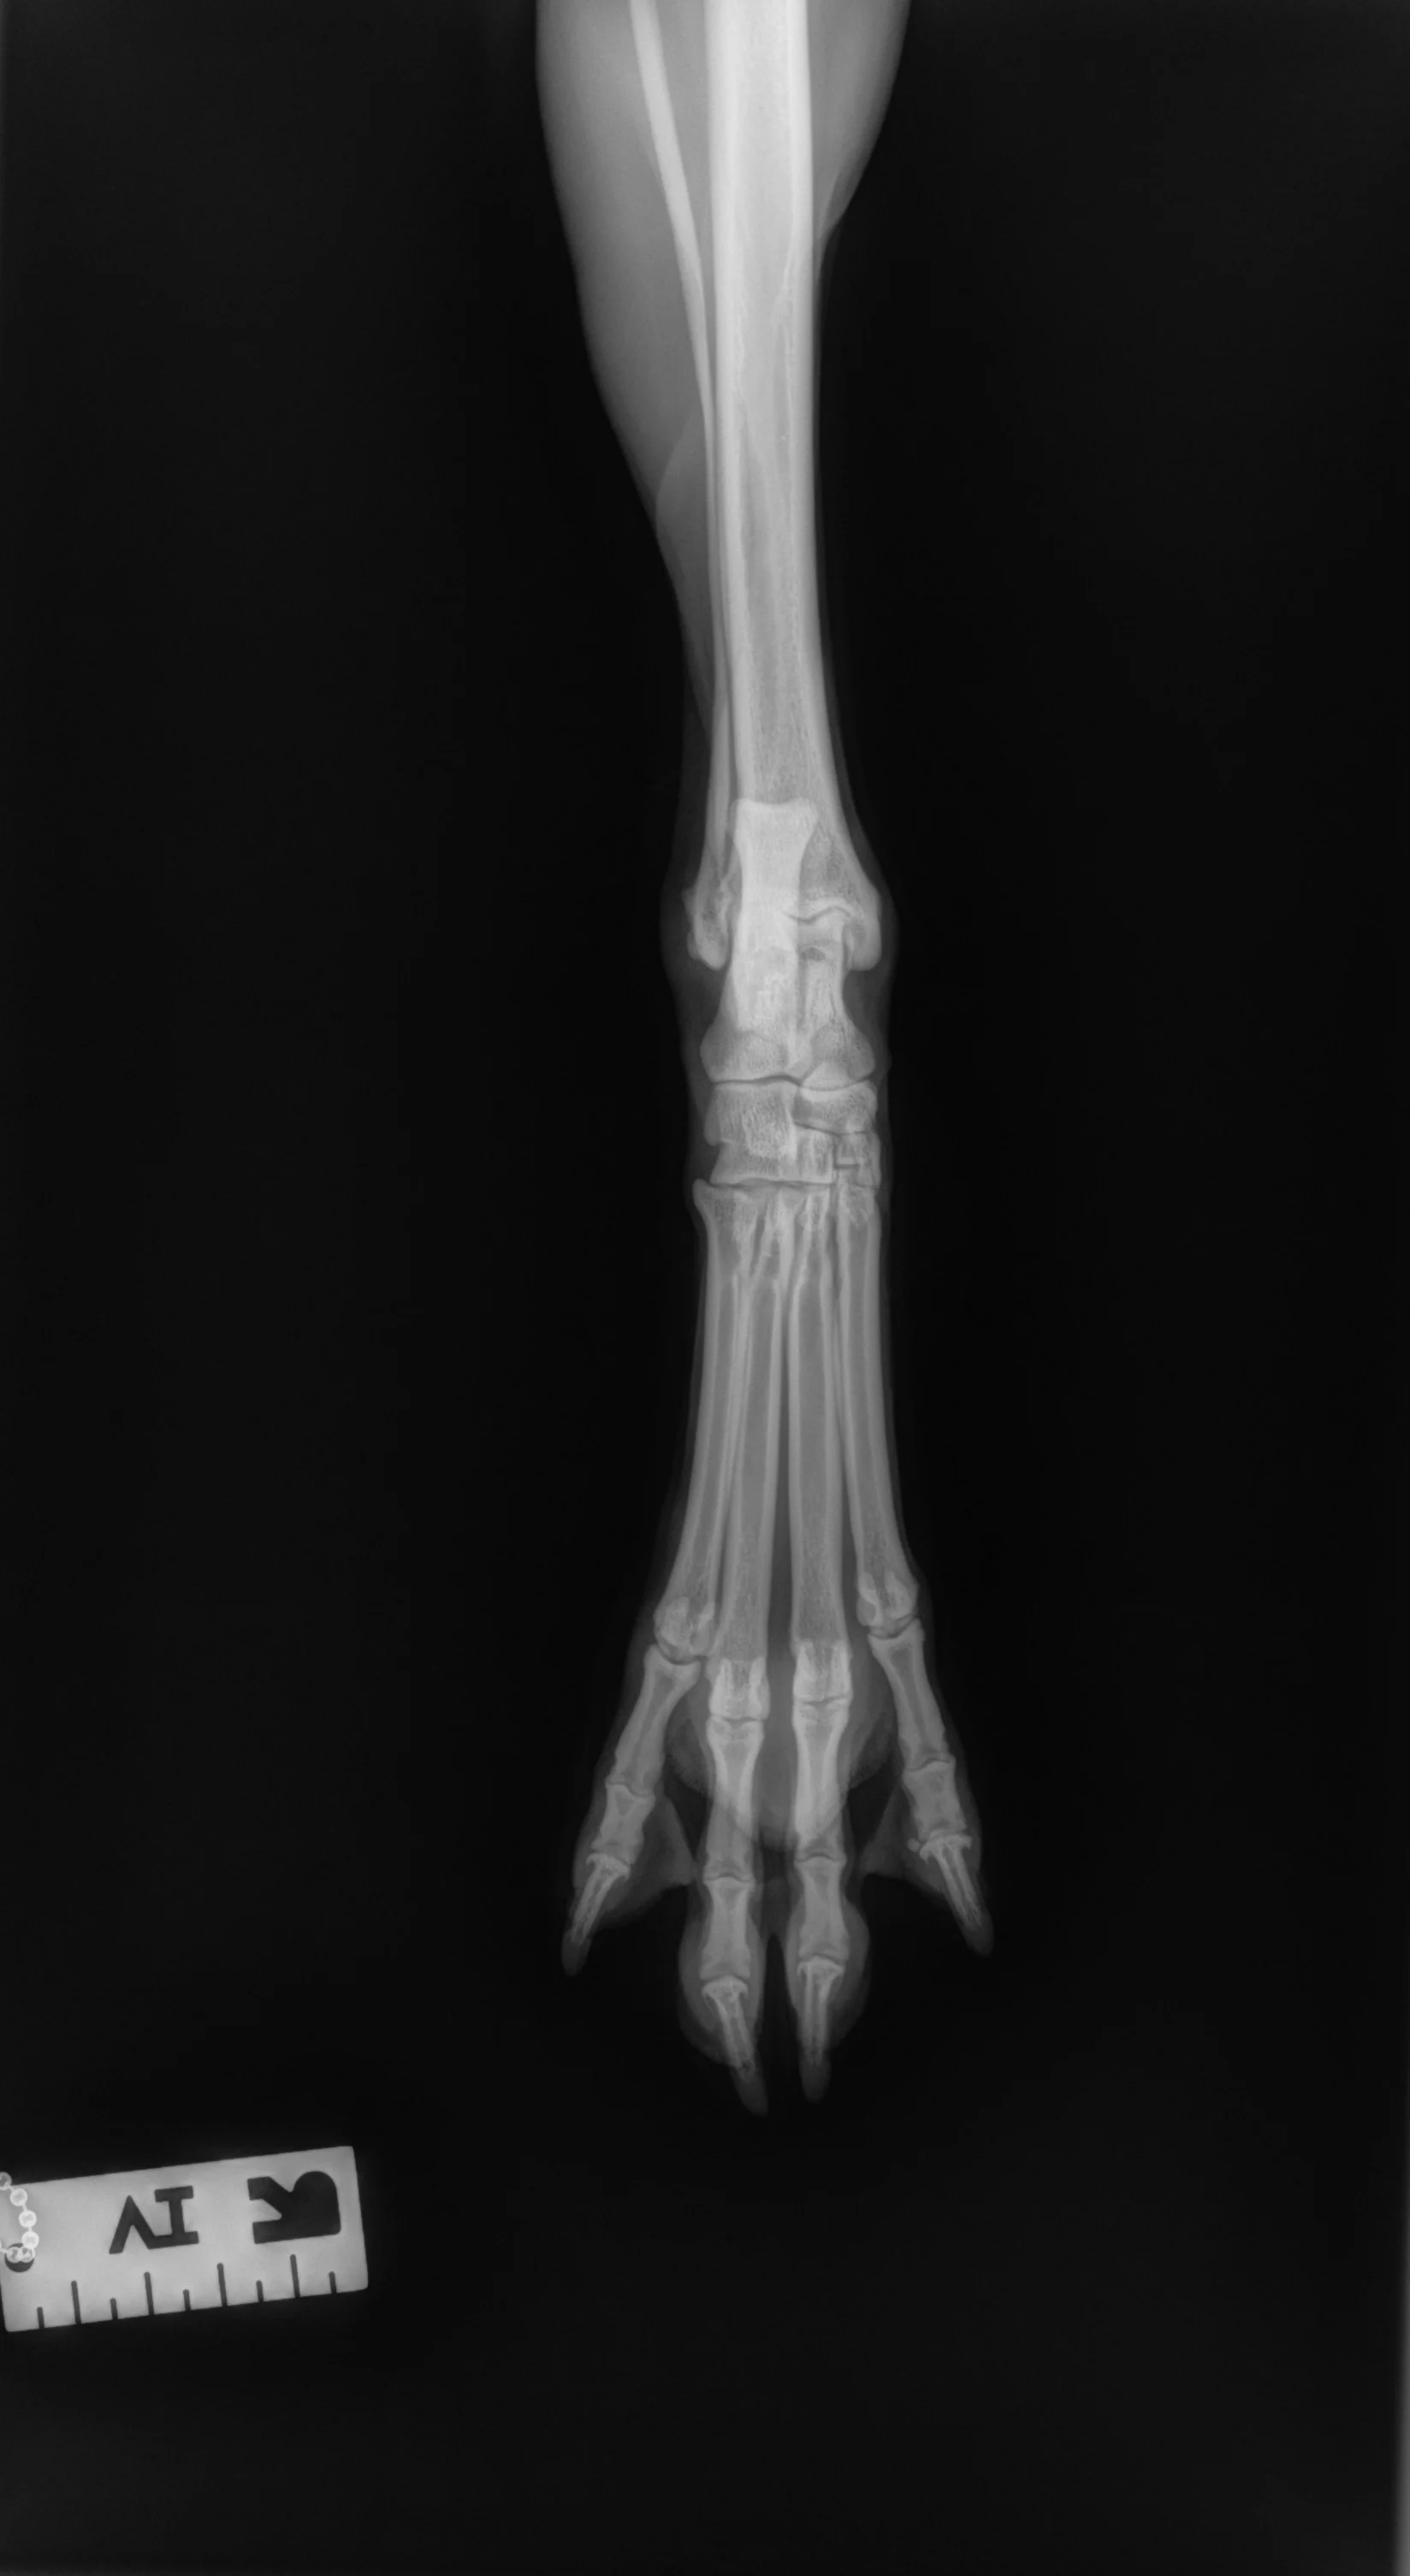

Step-by-Step: Positioning a Pelvic Limb for a Lateral View of the Digits

Step 1: Position the Patient

Place the patient in lateral recumbency with the affected limb on the table. Place a small object (eg, foam pad, gauze) under the calcaneus to keep the limb level and prevent overrotation of the limb and digits. Manually separate and tape down the digits (or use a wooden spoon to press, spread, and tape down the digits) to prevent to prevent superimposition on the radiograph—all digits should be visibly exposed and not overlap. Use a radiographic marker (eg, spherical ball marker, radiopaque numbered marker) to identify the different digits.

Step 2: Position the Beam

Center the collimator beam over the tarsometatarsal joints to include the distal metatarsals and all digits (the tarsus can also be included).

Author Insight

In these examples, the spherical marker ball was placed adjacent to digit V. Radiopaque numbered markers can also be used to individually identify each digit (not shown here). All digits should be separate and identifiable (arrows). The phalanges of each digit should be visible down through the toenail.